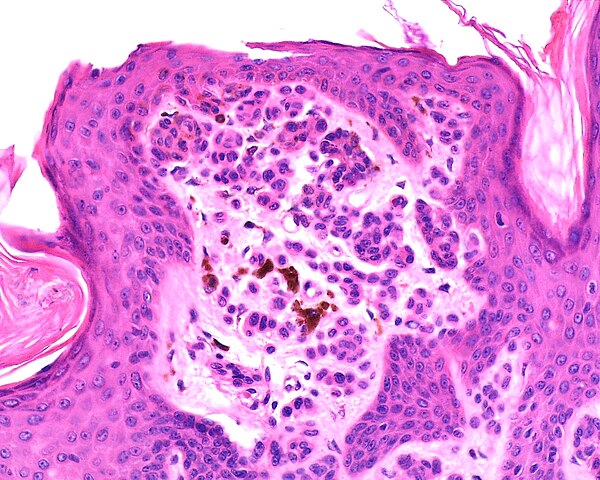

Skin biopsy taken from the lesion revealed hyperkeratosis, acanthosis, scattered melanocytes in the epidermis and lymphocytes and macrophages in the superficial dermis, but didn’t reveal any atypiaormitosis (Figure 1b).

Figure 1b

Hyperkeratosis, acanthosis, scattered melanocytes in theepidermis and lymphocytes and macrophages in the superficial dermis but didn’t revealanyatypiaormitosis.